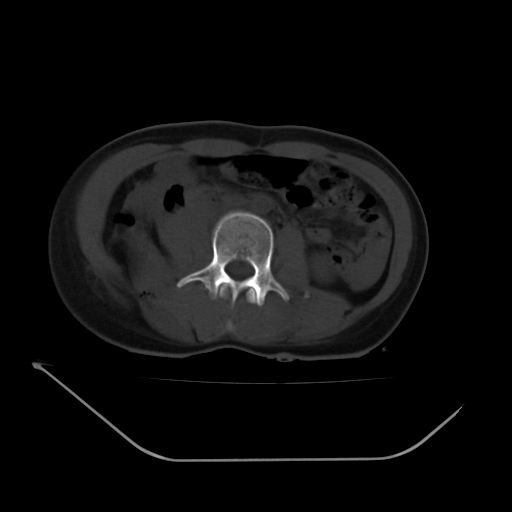

以下是引用liuyue在2008-7-19 13:02:00的发言:[br]1.肝右叶后下段及右肾挫裂伤伴腹腔积血。[br]2.右侧多发性肋骨骨折、横突骨折、右髂骨骨折伴周围软组织挫伤。[br]3.右侧腰大肌肿胀,并可见低密度影,如为气体,则肠道挫裂伤待除外。

以下是引用zhengfaming在2008-7-19 14:42:00的发言:[br]1.肝右叶后下段及右肾挫裂伤伴腹腔积血。脾脏挫裂伤待排[br]2.右侧多发性肋骨骨折、横突骨折、右髂骨骨折伴周围软组织挫伤。[br]3.右侧腰大肌肿胀,并可见低密度影,如为气体,则肠道挫裂伤待除外

以下是引用道哥在2008-7-19 16:52:00的发言:[br]肝右叶后下段及右肾挫裂伤、脾破裂伴腹腔积血。[br]2.双侧多发性肋骨骨折、横突骨折、右髂骨骨折伴周围软组织挫伤。[br]3.右侧腰大肌肿胀,并可见低密度影,如为气体,则肠道挫裂伤待除外。